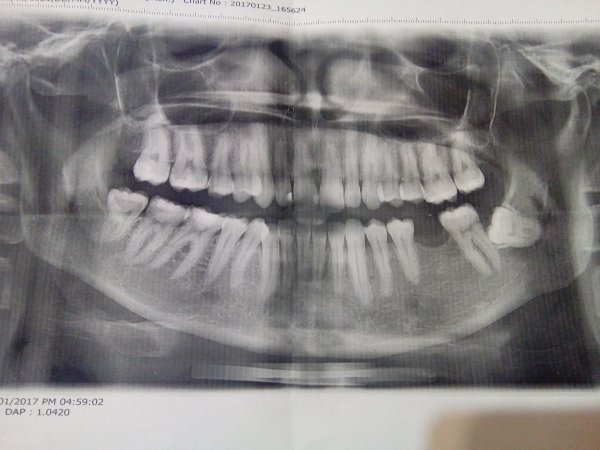

Беспокоит периодическая тянущая боль слева (от зубов к носу). Можно ли по снимку определить причину?

Комментарий №161934

• Внимательно изучил снимок, но стоматологических причин не увидел. Надо тщательно прощупать переходную складку слева и проекции верхушек корней. Затем, если выявится где-то болезненность, сделать прицельный снимок для лучшей четкости.